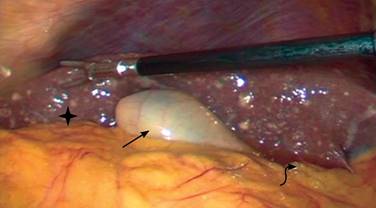

Se programó para laparoscopia diagnóstica teniendo los siguientes hallazgos: implantes hepáticos de primario desconocido, hepatomegalia, ascitis, vesícula biliar de pared delgada, sin cambios inflamatorios, por lo que se decide no efectuar colecistectomía al no tener indicación quirúrgica y ante los hallazgos mencionados con alta probabilidad de neoplasia. Se hizo toma de muestra de líquido peritoneal para estudio citológico y biopsia de implante hepático (Figura 3).

Figura 3: Imagen de laparoscopia diagnóstica donde se puede observar implantes hepáticos (asterisco), vesícula sin cambios inflamatorios (flecha recta) y ascitis (flecha curva).